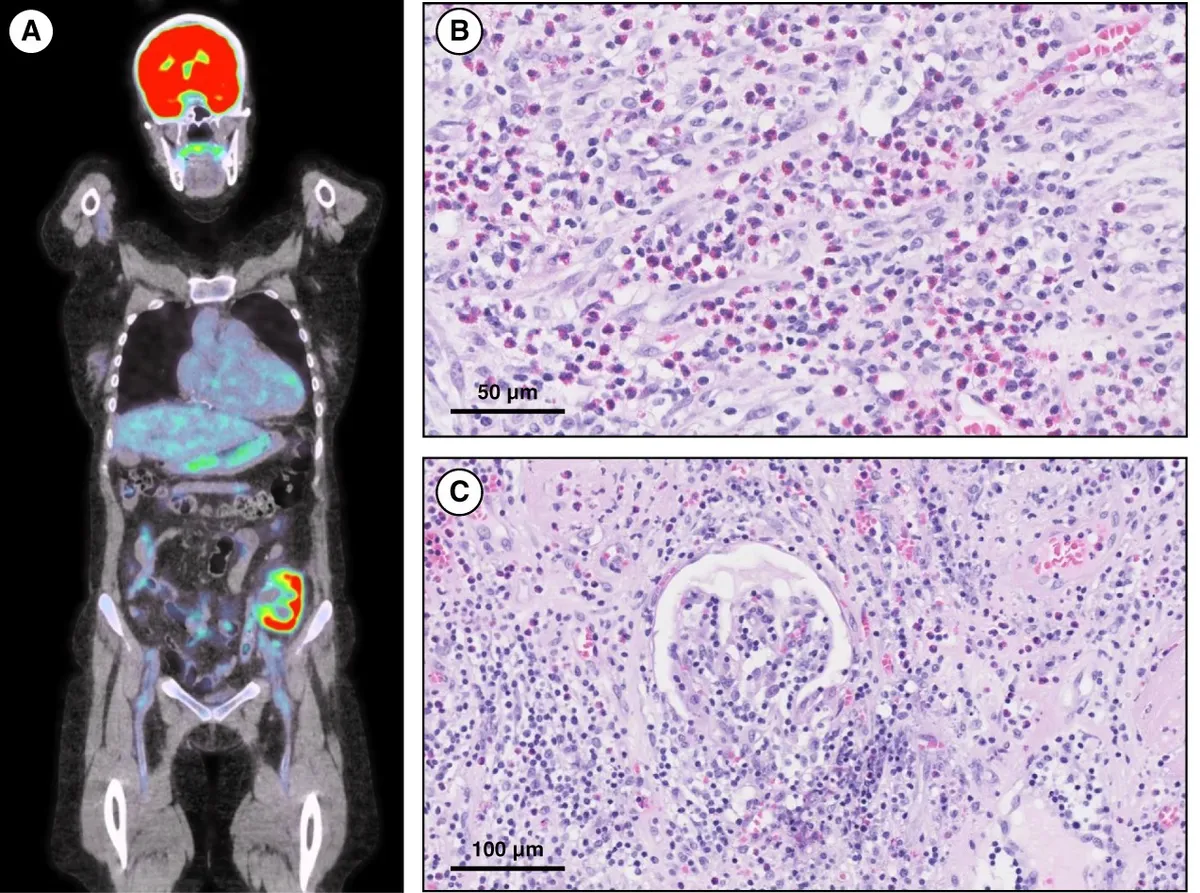

Foi realizado PET-CT que demonstrou atividade metabólica intensa no córtex do enxerto renal, sugerindo um quadro de rejeição aguda.

A biópsia do enxerto evidenciou inflamação intersticial significativa com infiltração por eosinófilos e linfócitos, glomerulite severa (g3), capilarite peritubular (ptc3) e contornos duplos na membrana basal glomerular (cg1). A coloração C4d foi positiva, confirmando rejeição mediada por anticorpos crônica ativa rica em eosinófilos.